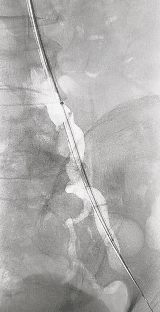

2.沿导丝交换BRITE TIP RADIANZ™ 经桡导引长鞘。导丝导管配合通过左髂动脉病变,交换Supracore导丝,沿导丝进入球囊8-60行预扩张,复查造影仍可见残余狭窄。

动脉长鞘怎么置入桡胜一筹丨吴巍巍主任、赵俊来教授团队:应用Brite Tip RADIANZ长鞘经桡动脉治疗下肢动脉粥样硬化闭塞症一例_https://www.jmylbn.com_新闻资讯_第17张

BRITE TIP RADIANZ 经桡导引长鞘

动脉长鞘怎么置入桡胜一筹丨吴巍巍主任、赵俊来教授团队:应用Brite Tip RADIANZ长鞘经桡动脉治疗下肢动脉粥样硬化闭塞症一例_https://www.jmylbn.com_新闻资讯_第18张

置入经桡导引长鞘

动脉长鞘怎么置入桡胜一筹丨吴巍巍主任、赵俊来教授团队:应用Brite Tip RADIANZ长鞘经桡动脉治疗下肢动脉粥样硬化闭塞症一例_https://www.jmylbn.com_新闻资讯_第19张

8-60球囊扩张